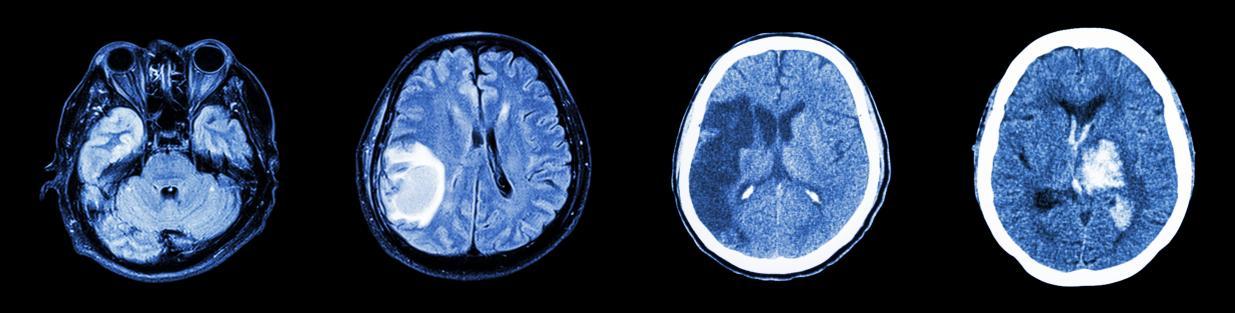

2.磁共振成像(Magnetic Resonance Imaging,MRI):

原理:利用强磁场和无线电波激发人体内氢原子产生信号,再转化为图像。

特点:无创、无X射线辐射,软组织分辨率高,能清晰显示脑组织细节。但检查时间较长(一般10~20分钟或更长),更适用于确诊脑梗死、脑肿瘤、炎症、白质病变等。

图2 版权图片 不授权转载

图3 版权图片 不授权转载